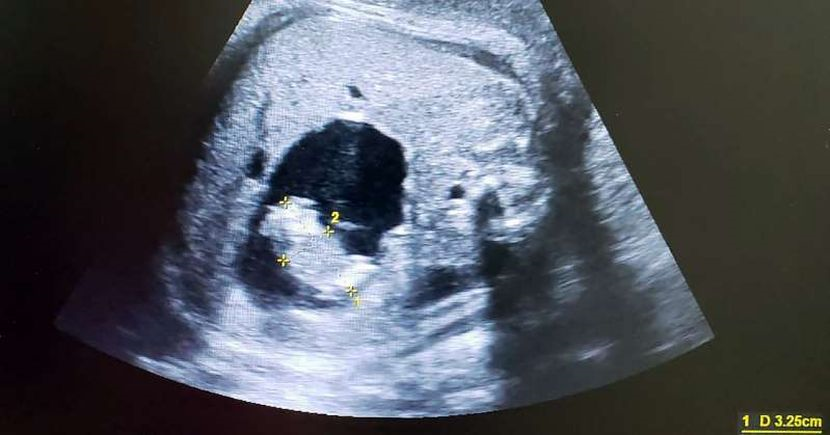

Imbasan yang dilakukan doktor.

Tetapi, menggunakan pengimejan ultrabunyi Doppler dan 3D/4D berwarna, Dr Parra-Saavedra dapat melihat bahawa ruang yang dipenuhi bendalir itu sebenarnya mengandungi 'bayi' kecil, disokong oleh tali pusat berasingan yang mana ia terhubung ke usus kembarnya yang lebih besar.